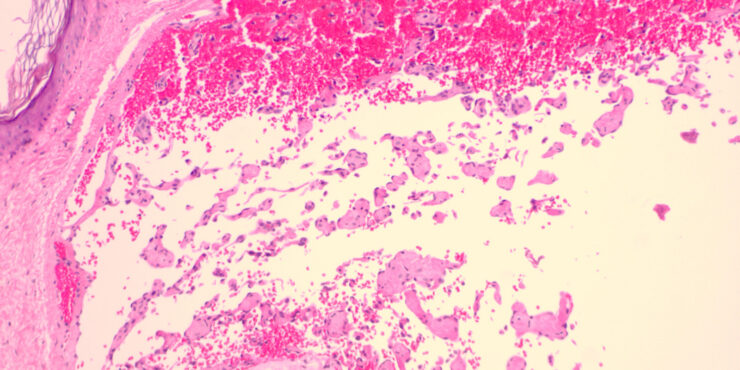

masson_tumor